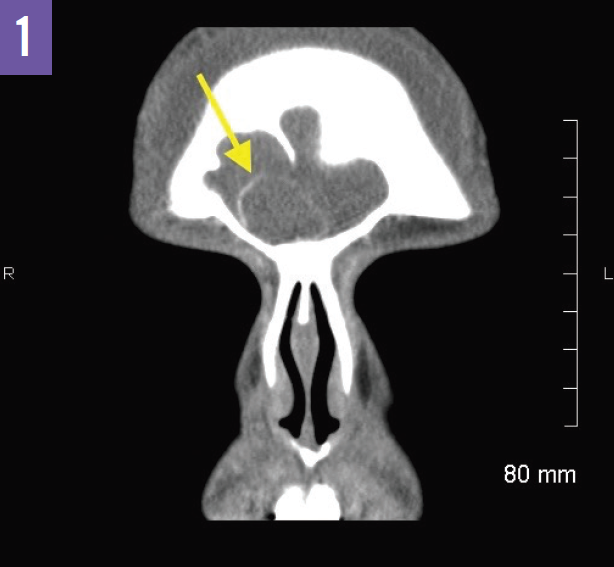

A contrast-enhanced CT of the sinuses performed after admission revealed complete opacification of the frontal sinuses and thinning of the inner table of the right frontal sinus. There was expansion of the bony margins of the right frontal sinus and a well-marginated collection in the right frontal sinus with a thin hyperdense rim (Figure 1). A thin-walled subgaleal collection was noted in the forehead at the midline overlying the outer table of the frontal sinuses (Figure 2). These CT findings were consistent with severe acute sinusitis with spread of infection into the soft tissues of the forehead and nasal bridge, or Pott puffy tumor. While there was no evidence of subdural empyema, a contrast-enhanced magnetic resonance imaging (MRI) scan of the brain was recommended to evaluate for subtle changes such as dural enhancement.